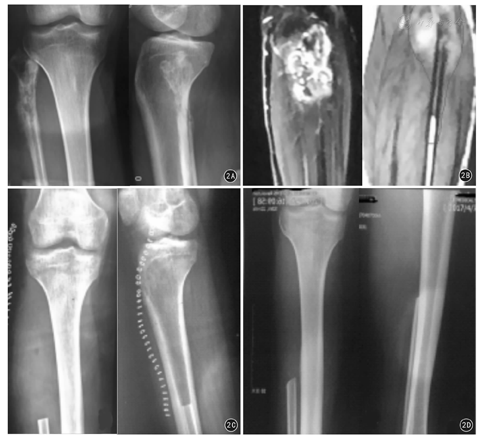

纳入2007年1月—2016年1月解放军东部战区总医院骨科腓骨近端骨肉瘤患者18例,其中男11例、女7例,中位年龄17(8~38)岁;左侧10例、右侧8例,Enneking外科分期ⅡB期17例、Ⅲ期1例。入院后均行患肢X线片、CT、MRI及胸部CT检查。X线片和CT可见腓骨近端骨质破坏,髓腔内浸润,多数患者可见日光样或放射状骨膜反应,伴有软组织肿块,其内可见高密度瘤骨。MRI可见腓骨近端被肿瘤浸润破坏后信号增高、骨皮质菲薄、中断,破坏区软组织占据。T1WI呈中低信号,T2WI呈中等偏高信号,瘤周水肿T2WI为高信号。

18例患者全部获得随访,随访时间7~120个月。8例出现肺部转移,死亡5例,另外3例患者截止末次随访时仍带瘤生存,皆进行口服阿帕替尼靶向治疗中。5例死亡患者中:1例入院即发生肺部转移,给予术后MTX化疗一次后患者肿瘤继续生长,2周后给予截肢手术,术后7个月死于肺衰竭;2例外院行非标准手术,导致局部间室污染,入院即行截肢手术,术后继续给予辅助化疗,分别于术后5、10个月发生肺部转移,并分别于术后8、12个月死于呼吸衰竭;2例接受Malawer type Ⅰ手术患者分别于术后18、36个月死于广泛肺转移引起的呼吸衰竭。15例保肢患者中1例出现术后伤口感染,给予积极加强换药,伤口正常愈合。复发4例皆为Malawer type Ⅰ手术患者,发现复发后均立即给予膝上截肢术。5例出现腓总神经损伤:其中2例患者术后2周神经麻痹症状逐渐自行好转,分别于术后3、7个月主诉症状基本消失;1例轻度跛行;2例Ⅱ型切除患者出现足下垂需佩踝关节支具行走。15例保肢手术患者无一例出现术后膝关节不稳症状表现,术后3个月MSTS功能评分显示术后膝关节功能良好11例、一般2例、差2例。患者具体资料见表1。典型病例见图1。